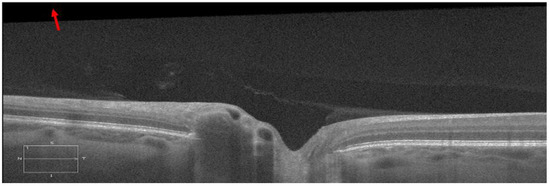

A misalignment between the OCT scan beam and the axis of the optic nerve during B-scan acquisition can result in significant image tilting [11]. Thus, the angle γ change could be significantly different between the left and right zone of the same B-scan, or even opposite after LP. For example, in Figure 3, the LP induced γ increased from −1.31° to 2.34° in the left zone, while it decreased from 2.44° to 0.77° in the right zone.

Figure 3. B-scans before and after LP in the temporal-nasal direction from the same individual. The blue dashed line marks the ppRPE/BM layer before LP, and the blue solid line marked the ppRPE/BM layer after LP. To visualize the angle γ change difference, the blue dashed line in the B-scan before LP was shifted vertically to the B-scan after LP.

This tilting artifact can be eliminated by averaging the ppRPE/BM layer angles of the left and right zones from the same cross-sectional B-scan. This averaged ppRPE/BM layer angle was referred to as the cross-sectional ppRPE/BM layer angle and denoted as Γ. A positive Γ indicates a V-shaped ppRPE/BM layer. The angle Γ in Figure 3 was 0.57° before LP, and increased to 1.56° after LP. In addition, this averaging method could also eliminate the artifact induced by the tilting of B-scan relative to the scanning window. Figure 4 illustrates one example in which the OCT scan had a tilt angle of 1.88° against the scanning window. The γ was measured as 4.78° in the left zone and −0.38° in the right zone. The angle Γ was calculated as 2.20°. After we readjusted the scan to its correct position by rotating an angle of 1.88° clockwise, the γ became 6.19° in the left zone and −1.98° in the right zone. The corresponding Γ was calculated as 2.11°, which was only 0.09° less than the one without tilt correction.